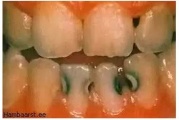

Lutipudelikaariese kahjustused

Lutipudelikaaries